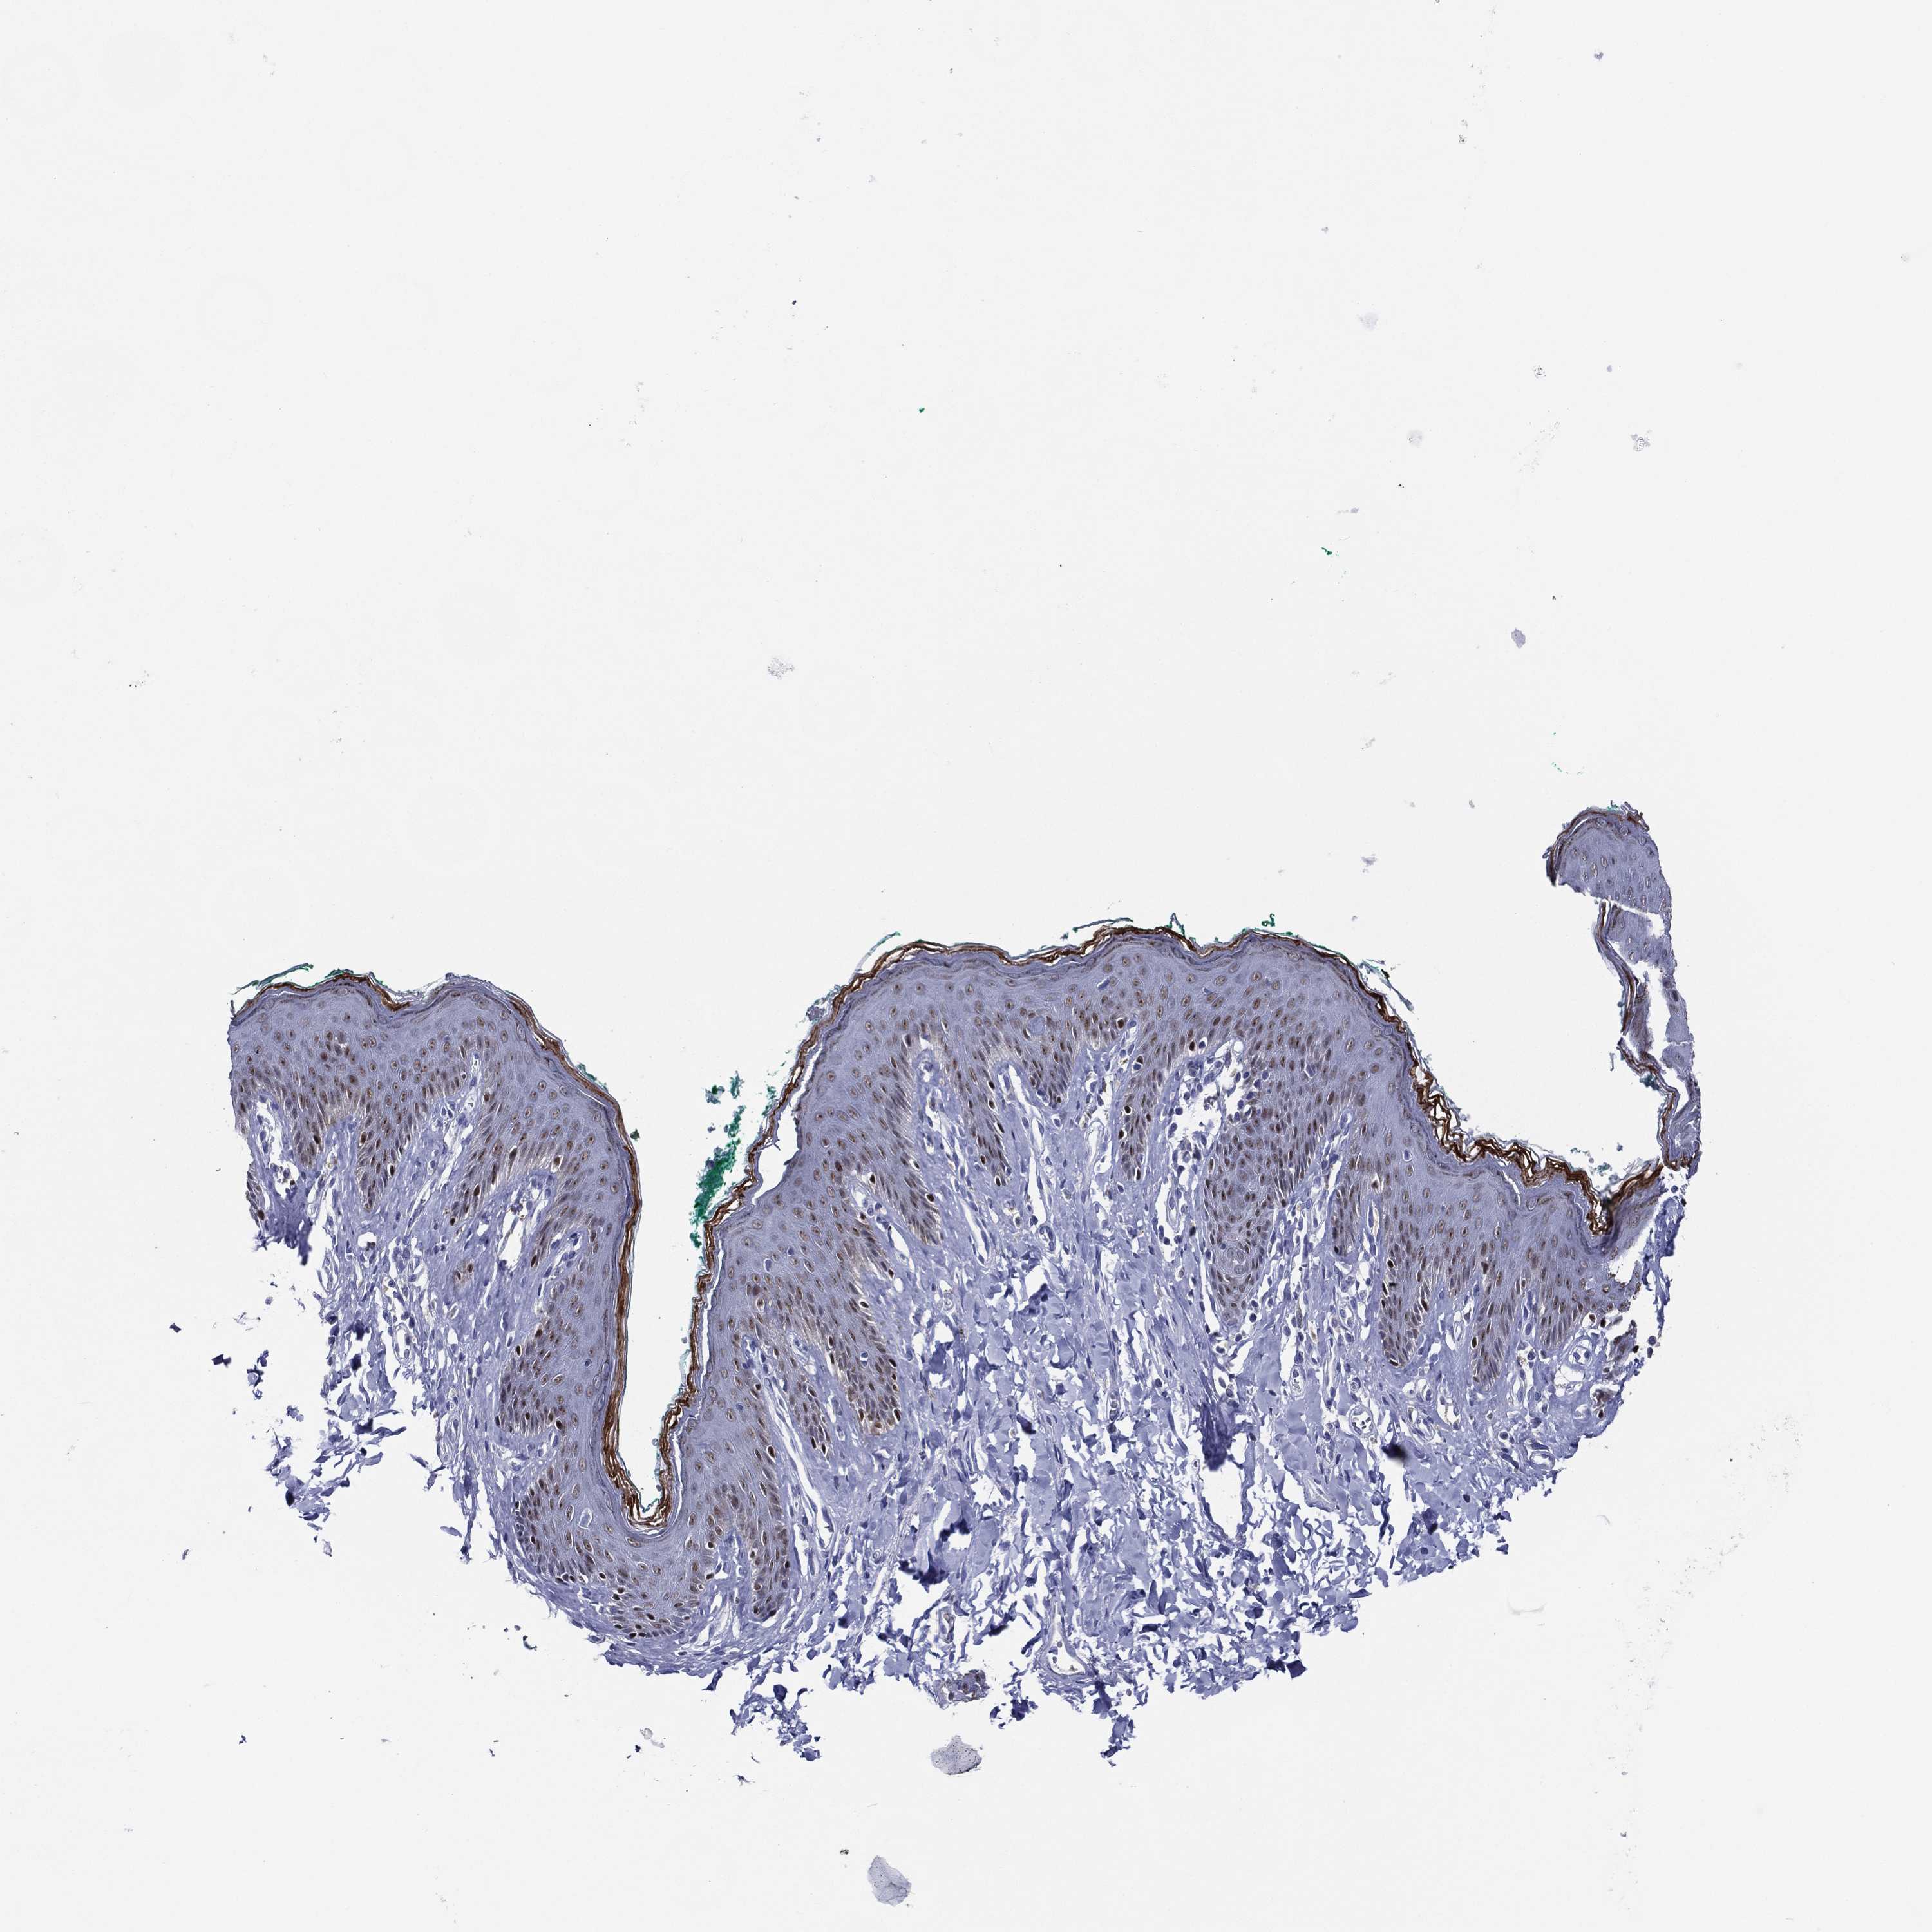

SKIN 1 - Antibody stainingi

Antibody staining in the annotated cell types in the current human tissue is reported as not detected, low, medium, or high, based on conventional immunohistochemistry profiling in selected tissues. This score is based on the combination of the staining intensity and fraction of stained cells.

Each image is clickable and will lead to virtual microscopy that enables deeper exploration of all samples and also displays staining intensity scores, fraction scores and subcellular localization as well as patient and tissue information for each sample.

Antibody HPA056871Antibody CAB000326

Langerhans Medium-

Cells in basal layer -Medium

Cells in corneal layer -Not detected

Cells in granular layer -Not detected

Cells in spinous layer -Medium

Endothelial cells -Not detected

Extracellular matrix -Not detected

Fibroblasts Not detected-

Fibrohistiocytic cells -Not detected

Keratinocytes Medium-

Langerhans cells -Medium

Lymphocytes -Not detected

Melanocytes Not detectedHigh

Vascular mural cells -Not detected